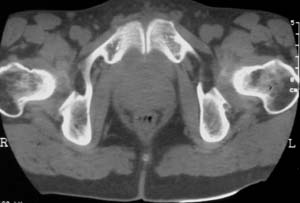

男,61岁,左侧髋关节疼痛,负重后更明显

现上传ct片

左侧股骨头增密,其内见有囊变密度减低区,关节面骨质硬化,关节间隙及髋臼无异示。考虑股骨头缺血坏死可能。建议mri检查。

我觉得股骨头未见到明显的问题,左侧股骨颈有卵圆形高密度影,考虑骨岛或骨梗死。

1\\左侧股骨颈有卵圆形高密度影,考虑骨岛或骨梗死。2\\由于临床症状疼痛,应该mri检查排除早期股骨头缺血坏死

左侧股骨颈处一卵圆形密度增高影,边界清,临近骨组织未见明显破坏.考虑为骨梗死,骨岛?